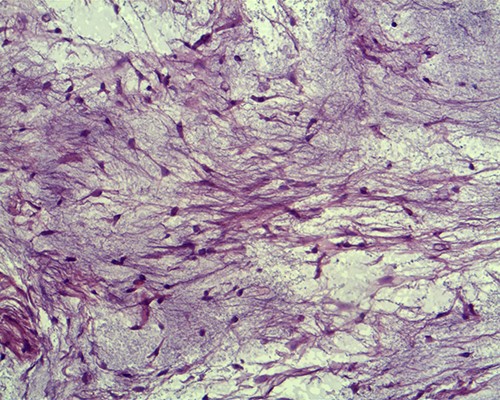

(a) Hypocellular myxoid tissue (periodic acid-Schiff staining, ×20). (b) The tumour contains strands of fibrocollagenous tissue (Van Gieson's staining).

Macroscopically, IMs typically appear as oval, grey-white, gelatinous masses with a firm consistency [1, 3]. Microscopically, the lesions are usually hypocellular and hypovascular [1, 5, 13] and contain spindle- and stellate-shaped cells with small, hyperchromatic nuclei that are embedded within an abundant myxoid stroma [1, 6]. Generally, mitotic activity and pleomorphism are absent [1, 5]. In our case, the histopathological results were consistent with these typical findings of IMs.